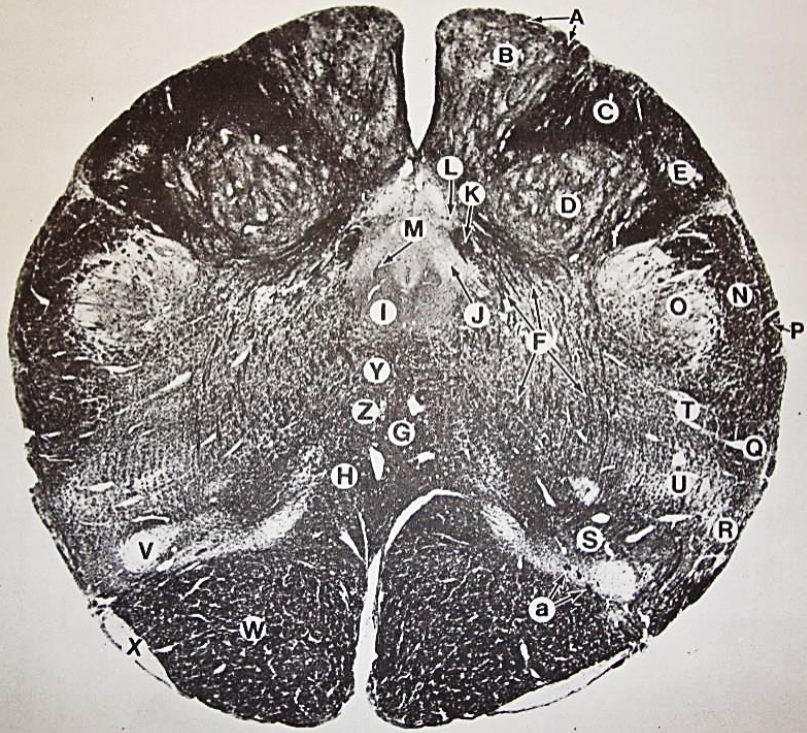

A

Lateral Cuneate nucleus

B

dorsal external arcuate fibers

C + D collectively

vestibular nuclei

C + D collectively

vestibular nuclei

E

dorsal motor nucleus of vagus nerve

F

solitary fasciculus

G

solitary nucleus

H

nucleus ambiguous

I

fascicles of glossopharyngeal nerve

J

hypoglossal nucleus

K

fascicles of hypoglossal nerve

L

dorsal longitudinal fasciculus

M

central tegmental tract

N

inferior olivary nucleus

R

inferior cerebellar peduncle

S

spinal trigeminal tract

T

spinal trigeminal nucleus

U

ventral trigeminothalamic tract

V

pyramidal (corticospinal) tract

W

rubrospinal tract

X

anterior spinocerebellar tract

Y

spinal lemniscus

Z

medial longitudinal fasciculus

a

tectospinal tract

b

medial lemniscus

c

vagus nerve

d

inferior salivatory nucleus